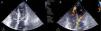

Durante a observação na unidade coronária mantinha sensação de mal‐estar e de lipotimia, apresentava‐se mais hipotensa e oligúrica. Na auscultação cardíaca constatou--se sopro holosistólico grau III/VI no bordo esquerdo do esterno. O ecocardiograma mostrou acinesia dos segmentos apicais e hipercontratilidade compensatória dos basais, com função sistólica global do ventrículo esquerdo (VE) conservada; diagnosticou‐se comunicação interventricular apical não restritiva (Figura 2) e ainda a presença de fluxo turbulento na câmara de saída do VE, com velocidade superior a 4m/s e movimento sistólico anterior do folheto anterior da válvula mitral (SAM) (Figura 3). Perante esta obstrução na câmara de saída do VE associada a hipotensão, decidiu‐se suspender a perfusão de dobutamina e administrar propranolol endovenoso. Verificou‐se melhoria sintomática e subida dos valores tensionais; no ecocardiograma observou‐se fluxo menos turbulento e de menor velocidade, e melhoria do SAM (Figura 4). Foi possível assim estabilizar a doente e transferi‐la para centro cirúrgico. Infelizmente, a doente faleceu devido a complicações na segunda semana do período pós‐operatório.

Ecocardiograma transtorácico a evidenciar fluxo turbulento apical (seta) devido à presença de rotura do septo interventricular (velocidades máximas registadas pelo Doppler contínuo inferiores a 3m/s).

AD: aurícula direita; AE: aurícula esquerda; VE: ventrículo esquerdo; VD: ventrículo direito.